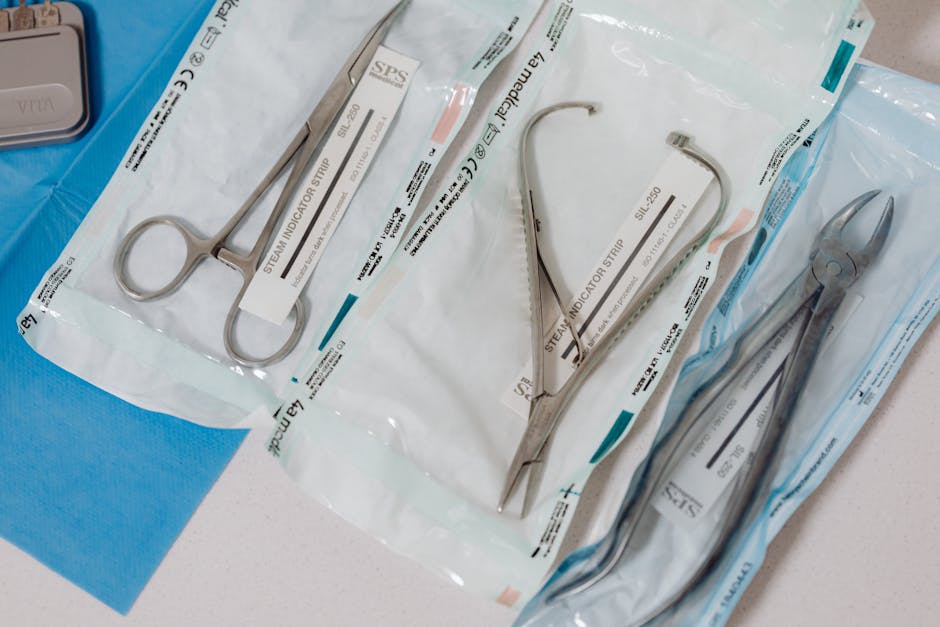

Instrumentação Cirúrgica

Esterilização E Medidas de Biossegurança